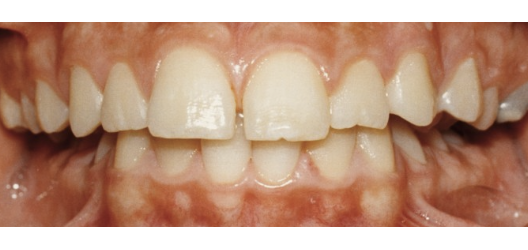

Wat is de klasse II-2 afwijking?

Hier spreken we van een dekbeet. Hierbij overlappen de voortanden in de bovenkaak de voortanden in de onderkaak.